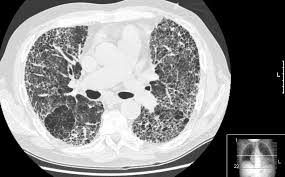

This test is most often used to look at the chest and/or belly (abdomen) to see if breast cancer has spread to other organs. Not necessarily is the whole body going to be scanned at that time. Once a nodule is found, a workup is done to see if it is cancer. If i had contrast on the earlier ct, my cancer would have been found 2 1/2 years earlier. Help check how well treatment is working and/or.

Review Of Methods For Intraoperative Margin Detection For Breast Conserving Surgery from www.spiedigitallibrary.org Ct scans of the chest are used to find lung nodules or other chest pathology. Before the scan, you will either drink a liquid dye or be given an injection of dye into a vein in your arm. Further, its diagnostic reach can go beyond the bone. Each picture created during a ct procedure. It can damage the dna in your cells and raise the chance that they'll turn cancerous. In contrast with bone scans, which are only able to detect bone metastases, pet/ct has the advantage of concurrently imaging other common sites of breast cancer metastases such as the liver and lungs, says lead author patrick morris, a breast cancer specialist at memorial sloan kettering. Other names for this test: A female patient came to see me with some difficulty swallowing, a very routine issue for a gastroenterologist.

Ct scans can help doctors: If you have a large breast cancer, your doctor may order a ct scan to assess whether or not the cancer has moved into the chest wall. This substance is often called a tracer, because it helps reveal cancer in the body. The scan lets them:learn the cancer's stage. Computed tomography scan, ct scan, cat scan, and spiral or helical ct. 234 views answered >2 years ago Before the scan, you will either drink a liquid dye or be given an injection of dye into a vein in your arm. Breast cancer affects over 200,000 women each year. A pelvic ct scan can be used to detect several types of cancer. Contrast medium is a dye that helps body tissues show up more clearly on the scan. In contrast with bone scans, which are only able to detect bone metastases, pet/ct has the advantage of concurrently imaging other common sites of breast cancer metastases such as the liver and lungs, says lead author patrick morris, a breast cancer specialist at memorial sloan kettering. You are encouraged to drink clear liquids. This helps determine whether or not the cancer can be removed with mastectomy.

In general breast cancer can be detected on a routine chest ct scan regardless of if contrast media is used or not. Several types of cancer can form in the breast, making it the second most common cancer that affects american women. These scans expose you to more. Before a pet/ct scan, an iv that injects a small amount of a radioactive substance will be placed into one of your veins. Long story short i have a ct scan with contrast on 1st june to look for cancer in the abdominal cavity.

Advanced Radiology Consultants Fast Breast Mri from www.adrad.com The term tomography comes from the greek words tomos (a cut, a slice, or a section) and graphein (to write or record). They may also use it to learn more about the cancer after they find it. If i had contrast on the earlier ct, my cancer would have been found 2 1/2 years earlier. When a ct scan misses cancer. Breast cancer affects over 200,000 women each year. If you have a large breast cancer, your doctor may order a ct scan to assess whether or not the cancer has moved into the chest wall. A ct scan may be used to: Therefore, ct scans can lead to a false negative this can negatively impact your ability to get any treatment at all this can prolong the time it takes you to access treatment